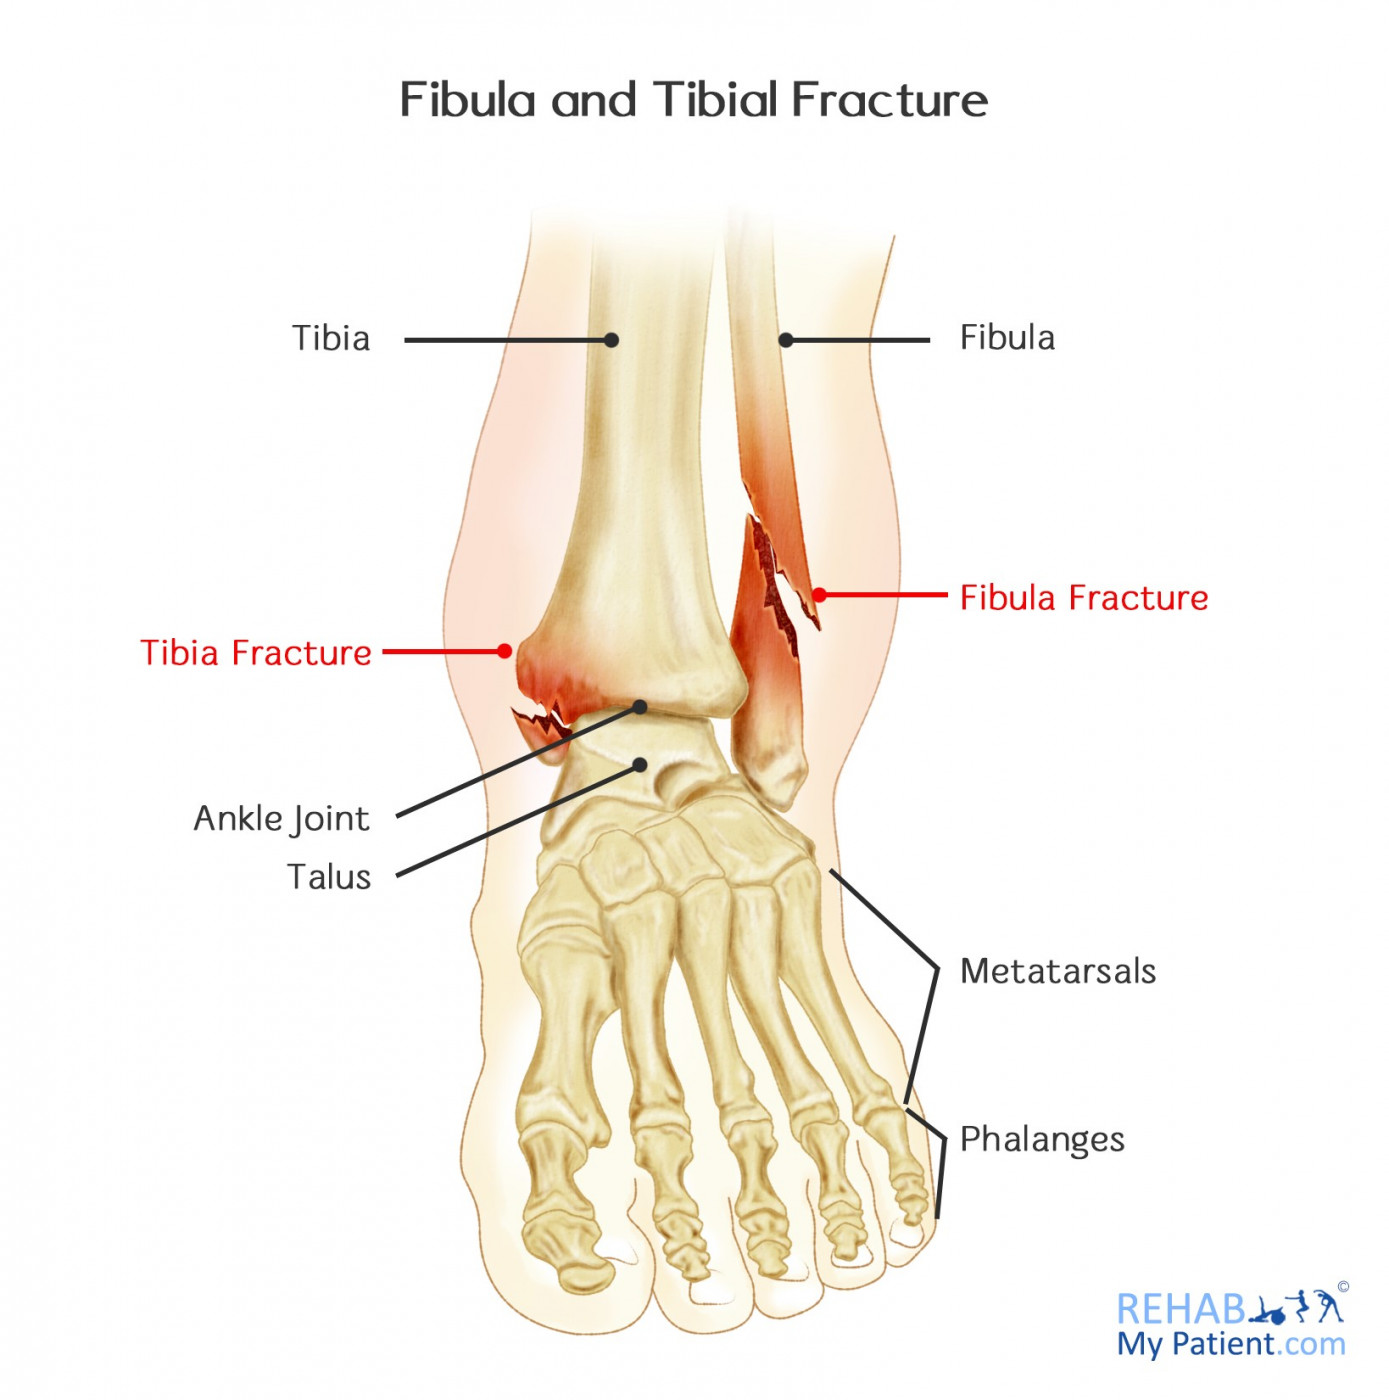

Fibula and Tibial Fracture | Rehab My Patient

Broken or Sprained Ankle? – Pontchartrain Orthopedics & Sports Med

Fractured Tibia and Fibula (Broken Lower Leg Bones) with Fixation …

AP ( a ) and lateral ( b ) radiographs show a distal fibula fracture …

Cureus | Osteoporotic Distal Fibula Fractures in the Elderly: How To …

Ankle X-ray Interpretation | Ankle Fracture | Geeky Medics

Ankle Fracture | footEducation | Ankle fracture, Broken ankle recovery …